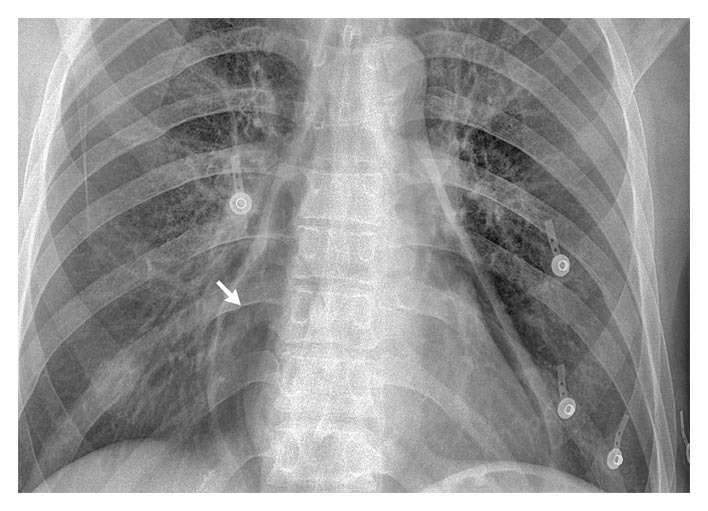

A 47-year-old homeless man presented to the emergency department 1 week after the onset of chest pain. He was hemodynamically stable. The physical examination was unremarkable.

A routine complete blood count revealed 27,000 leukocytes per cubic millimeter. A chest radiograph showed pneumopericardium (arrow) without evidence of pneumothorax or pneumomediastinum.